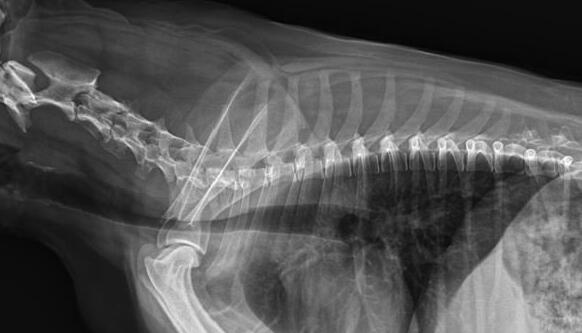

獸用dr拍攝效果圖

利用寵物dr拍攝圖像效果圖

獸用dr是一款專用于寵物X光拍攝的數字化X射線檢查設備,把穿透寵物的X線信息轉化為數字信號,并由計算機重建圖像及進行一系列的圖像后處理。相比傳統的ct,從圖像的畫質到精確度都比較高,因此,更加便于醫生進行診斷。不僅僅如此,獸用dr還有哪些特點呢?普愛醫療小編來詳細介紹。